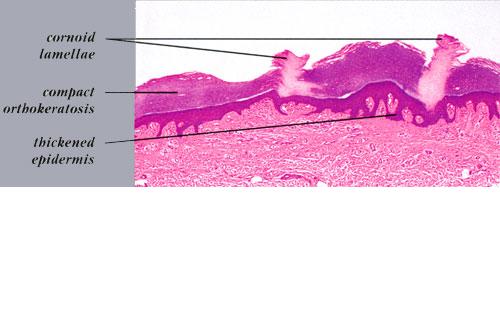

Histopathologic patterns are similar in all forms of porokeratosis, with the characteristic changes evident at the raised and advancing edge of the lesion. The stratum corneum is hyperkeratotic, with a thin column of poorly staining parakeratotic cells, the cornoid lamella, running through the surrounding normal-staining cells . The underlying keratinocytes are edematous with spongiosis and shrunken nuclei, and a striking dermal lymphocytic pattern may be evident. Underlying the cornoid lamella, the granular layer is either absent or markedly reduced but is of normal

thickness in other areas of the lesion. The epidermis in the central portion of porokeratosis may be normal, hyperplastic, or atrophic. Although characteristic of porokeratosis, the cornoid lamella is not pathognomonic and may also be found in other conditions, such as viral warts, some ichthyoses, and nevoid hyperkeratoses.